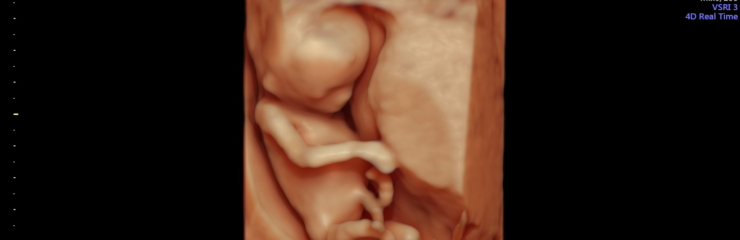

Плод:

Плод весит около 450 граммов и активно двигается. У него уже есть брови и ресницы. Чаще всего плод наиболее активен тогда, когда женщина отдыхает. Начинают расти первые настоящие волосы.

Шейные позвонки хорошо видны. На 23-й неделе плод весит примерно 550 граммов. С 23-й недели на 4D-ультразвуковом исследовании уже можно хорошо рассмотреть черты лица плода.

- По желанию — 4D-ультразвуковое исследование (24–32 недели)

Вес плода составляет примерно 1 килограмм, длина — около 35 сантиметров. Это лучшее время для наблюдения лица плода с помощью 4D-ультразвукового исследования.

Это время, когда стоит постепенно начинать думать о родах и обсудить, кого женщина хотела бы видеть в качестве сопровождающего на родах. В этот период можно вместе сходить на 4D-ультразвуковое исследование, которое даёт информацию о здоровье и развитии ребёнка, а также позволяет будущим родителям наблюдать за своим малышом в реальном времени, вызывая радость и положительные эмоции.